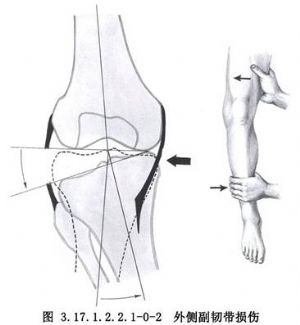

新鮮膝外側副韌帶修補術用於外側副韌帶損傷的手術治療。外側副韌帶對膝關節的穩定沒有內側副韌帶那麼重要,其損傷也較少見,原因是在屈曲位時外側副韌帶鬆弛,不致因旋轉應力受傷,伸膝位時又爲髂脛束、股二頭肌腱、外側關節囊、交叉韌帶所加強,也受到對側肢體保護免受內收位損傷。僅在膝關節輕度屈曲時關節承受內翻應力,可損傷其外側結構,包括髂脛束、外側副韌帶、外側關節囊、膕肌腱、交叉韌帶、股二頭肌、腓腸肌外側頭、腓總神經等(圖3.17.1.2.2.1-0-1~3.17.1.2.2.1-0-3)。

膝外側結構損傷,應採用正確的方法及時治療,否則會導致膝前外側旋轉不穩定。對關節影響嚴重者,或合併外側半月板及前交叉韌帶損傷者,需行韌帶重建術。但是,慢性膝外側韌帶鬆弛在治療上仍是個難題,遠期療效不甚理想。有時用腓腸肌外側頭的一部分或一條闊筋膜等方法可增強側方結構的穩定性。